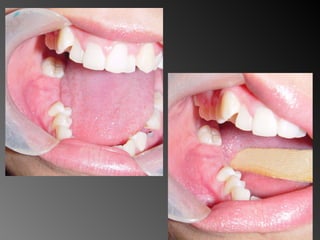

25 - L.C.S., sexo masculino, 18 anos de idade, se apresentou com queixa de aumento de volume na gengiva entre os dentes 23 e 24. Pelo exame clínico, constatamos a presença de um nódulo séssil, de contornos irregulares, coloração avermelhada, com sangramento abundante ao mínimo toque e evolução de 1 ano. O paciente apresentava higiene bucal precária com presença de placa bacteriana e tártaro. Com base no quadro clínico, o diagnóstico é: a) Fibroma e granuloma piogênico. b) Granuloma piogênico e hiperplasia fibrosa inflamatória. c) Lesão periférica (granuloma) de células gigantes e fibroma. d) Granuloma piogênico e lesão periférica (granuloma) de células gigantes. e) Hiperplasia fibrosa inflamatória e fibroma.

Granuloma Piogênico Lesõesnodulares de coloração avermelhada ou vinhosa Provavelmente uma reação inflamatória exagerada ao trauma menor Crescimento rápido, às vezes sangramento espontâneo Ocorre em qualquer idade mas parece mais freqüente em adultos jovens e adolescentes Localização mais comum: gengiva (NEVILLE,2001)

Granuloma Periférico deCélulas Gigantes Lesões nodulares de coloração avermelhada ou vinhosa Provavelmente uma reação inflamatória exagerada ao trauma menor Crescimento rápido, às vezes sangramento espontâneo Ocorre em qualquer idade mas parece mais freqüente em homens antes dos 16 anos de idade a após esta faixa torna-se duas vezes mais freqüente em mulheres Localização mais comum: gengiva